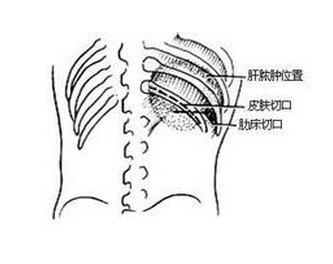

(三)切开引流 适用于较大脓肿、估计有穿破可能,或已经穿破胸腔或腹腔;胆源性肝脓肿;位于肝脏左外叶的肝脓肿,穿刺容易污染腹腔,不宜穿刺,可选择切开引流;慢性肝脓肿,病情较为复杂,考虑切开引流治疗。

2.肝穿刺引流: 早期选用有效药物治疗,不少肝脓肿已无穿刺的必要。对恰当的药物治疗5~7天、临床情况无明显改善,或肝局部隆起显著、压痛明显,有穿破危险者采用穿刺引流。穿刺最好于抗阿米巴药物治疗2~4天后进行。穿刺部位多选右前腋线第8或第9肋间,或右中腑线上第九或十肋间或肝区隆起、压痛最明显处,最好在超声波探查定位下进行。穿刺次数视病情需要而寂静,每次穿刺应尽量将脓液抽净,脓液量在200ml以上者常需在3~5天后重复抽吸。脓腔大者经抽吸可加速康复。近年出现的介入性治疗,经导针引导作持续闭合引流,可免去反复穿刺、继发性感染之缺点,有条件者采用。

肝脓肿需手术引流者一般<5%。其适应证为①抗阿米巴药物治疗及穿刺引流失败者;②脓肿位置特殊,贴近肝门、大血管或位置过深(>8cm),穿刺易伤及邻近器官者;③脓肿穿破入腹腔或邻近内脏而引流不畅者;④脓肿中有继发细菌感染,药物治疗不能控制者;⑤多发性脓肿,使穿刺引流困难或失败者;⑥左叶肝脓肿易向心包穿破,穿刺易污染腹腔,也应考虑手术。